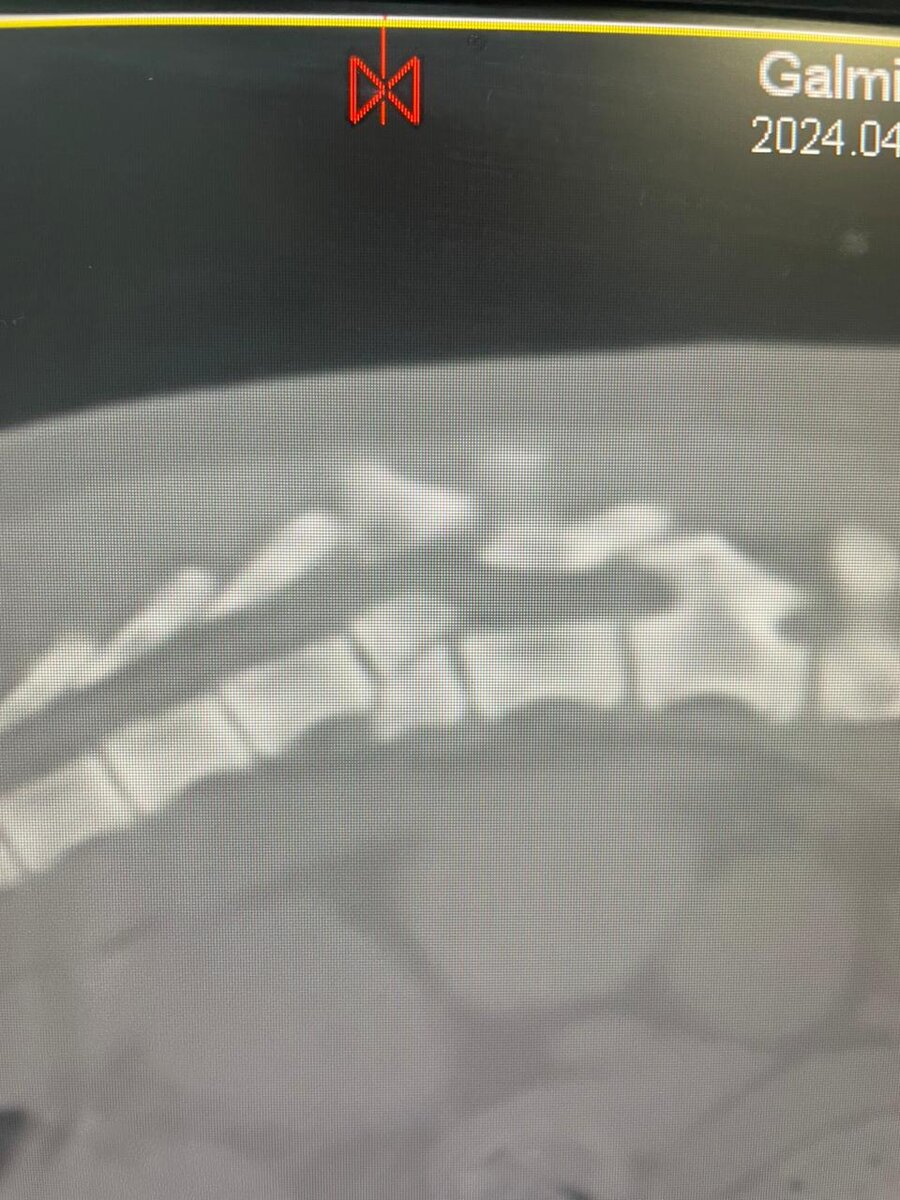

Снимок КТ позвоночника Снежки

Как вы помните, шестимесячную Снежечку сбила машина, водитель скрылся, а бедная девчонка получила огромное множество травм и переломов, в том числе и сложный перелом позвоночника. Уже в воскресенье у Снежки должна была состояться операция стоимостью АЖ ОКОЛО 70 000 РУБЛЕЙ, только вчера за стационар мы оплатили ЦЕЛЫХ 20 000 РУБЛЕЙ, и это не считая питания, а находиться в стационаре ей предстоит КАК МИНИМУМ до операции, то есть, до воскресенья, и собрать средства для спасения нашей бедной малышки, как оказывается, НЕВОЗМОЖНО!!! За время пребывания Снежки в стационаре УЖЕ было оплачено около 50 000 рублей, процедура КТ обошлась нам ещё в 20 000 рублей!!!